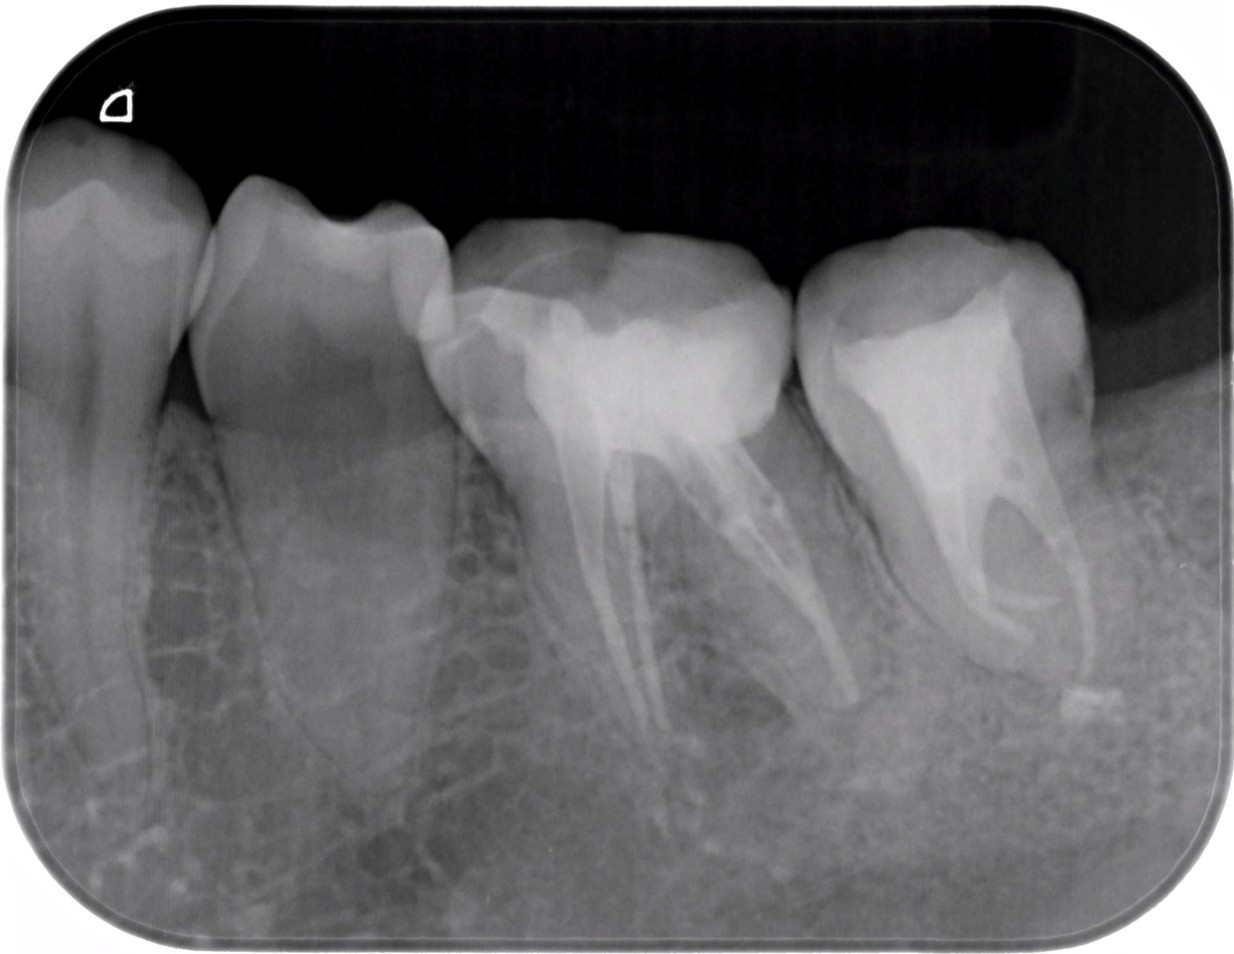

| 患者様データ | 40代 男性 |

| 来院時の主訴 | 「左下が痛くて噛めない。」 |

| 医院の診断 | 左下第一大臼歯歯根破折、慢性根尖性歯周炎 |